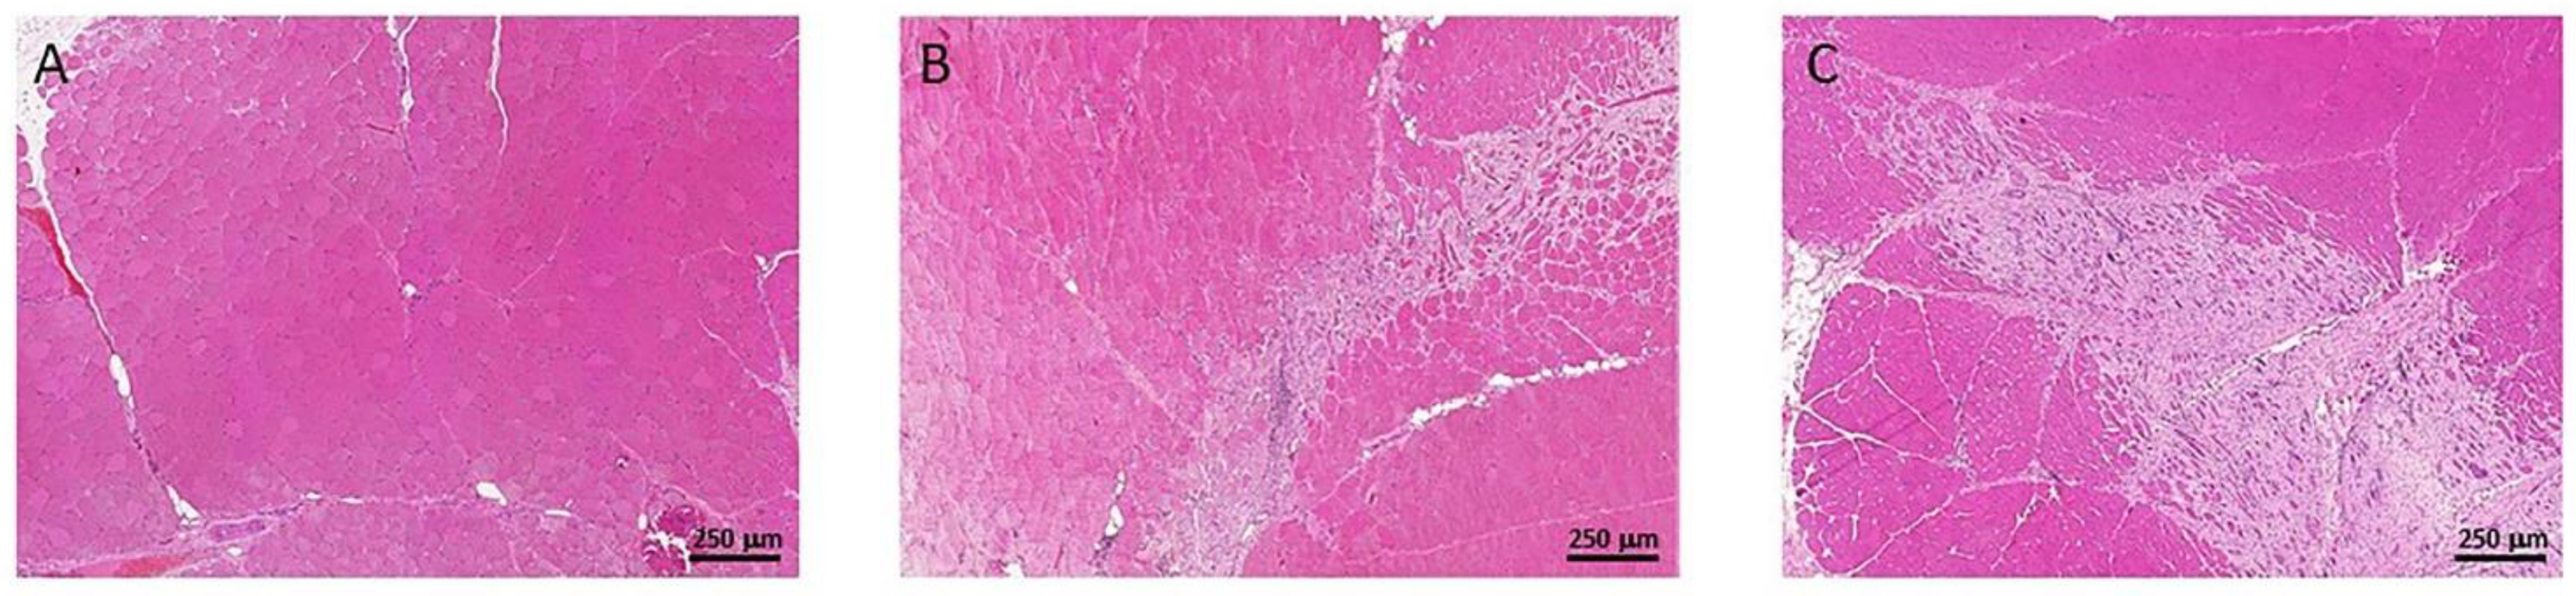

3.3. Muscle Fibrosis